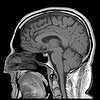

Courts continue to flirt with admitting fMRI evidence into court. While brain imaging techniques are uncovering great new information, it is not clear to me if they will ever be accurate enough to distinguish truth-telling from lying.

Wired Science has covered a legal case where fMRI brain scan lie detection data was offered as evidence. While the lawyer was initially hopeful, it was ruled inadmissible by the judge on the basis that judgements of witness credibility by the jury should be based on their impression of the witness.